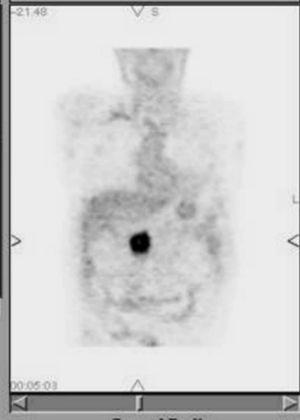

Tomografía por emisión de positrones

La tomografía por emisión de positrones permite la realización de un rastreo de «cuerpo entero» que tiene la ventaja de poder demostrar metástasis a distancia en lugares insospechados que modifiquen la indicación terapéutica en algunos casos65. Por otra parte, la tomografía por emisión de positrones (PET) es especialmente útil en el seguimiento de los pacientes con cáncer de páncreas, en los que las alteraciones anatómicas posterapéuticas dificultan la valoración locorregional de la recidiva tumoral en los estudios de TC y RM (fig. 13). En los casos en los que estas técnicas muestran hallazgos poco concluyentes, la PET tiene una clara indicación66. La posibilidad de combinar un equipo de PET con un equipo de TC (PET/TC)67 abre nuevas expectativas para el diagnóstico, estadificación y seguimiento del adenocarcinoma ductal pancreático.

Fig. 13.--Tomografía por emisión de positrones. Reconstrucción coronal que muestra una intensa captación de fluorodesoxiglucosa en el lecho quirúrgico, correspondiente a una recidiva tumoral en un paciente tratado mediante duodenopancreatectomía cefálica.